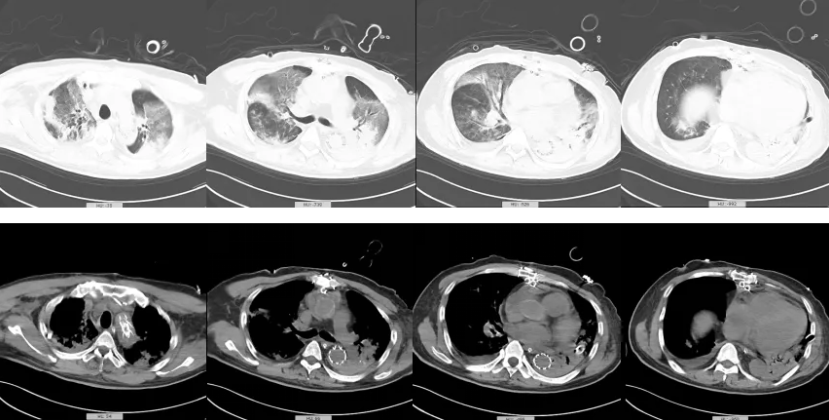

入院复查肺CT(图2):双肺多发实变及斑片状浸润影,以左下肺为著。心包纵隔引流、双侧胸腔闭式引流置管状态。主动脉夹层术后,主动脉瓣换瓣术后状态。

图2. 胸CT提示:双肺多发实变及斑片状浸润影,以左下肺为著。心包纵隔引流、双侧胸腔闭式引流置管状态。主动脉夹层术后,主动脉瓣换瓣术后状态。